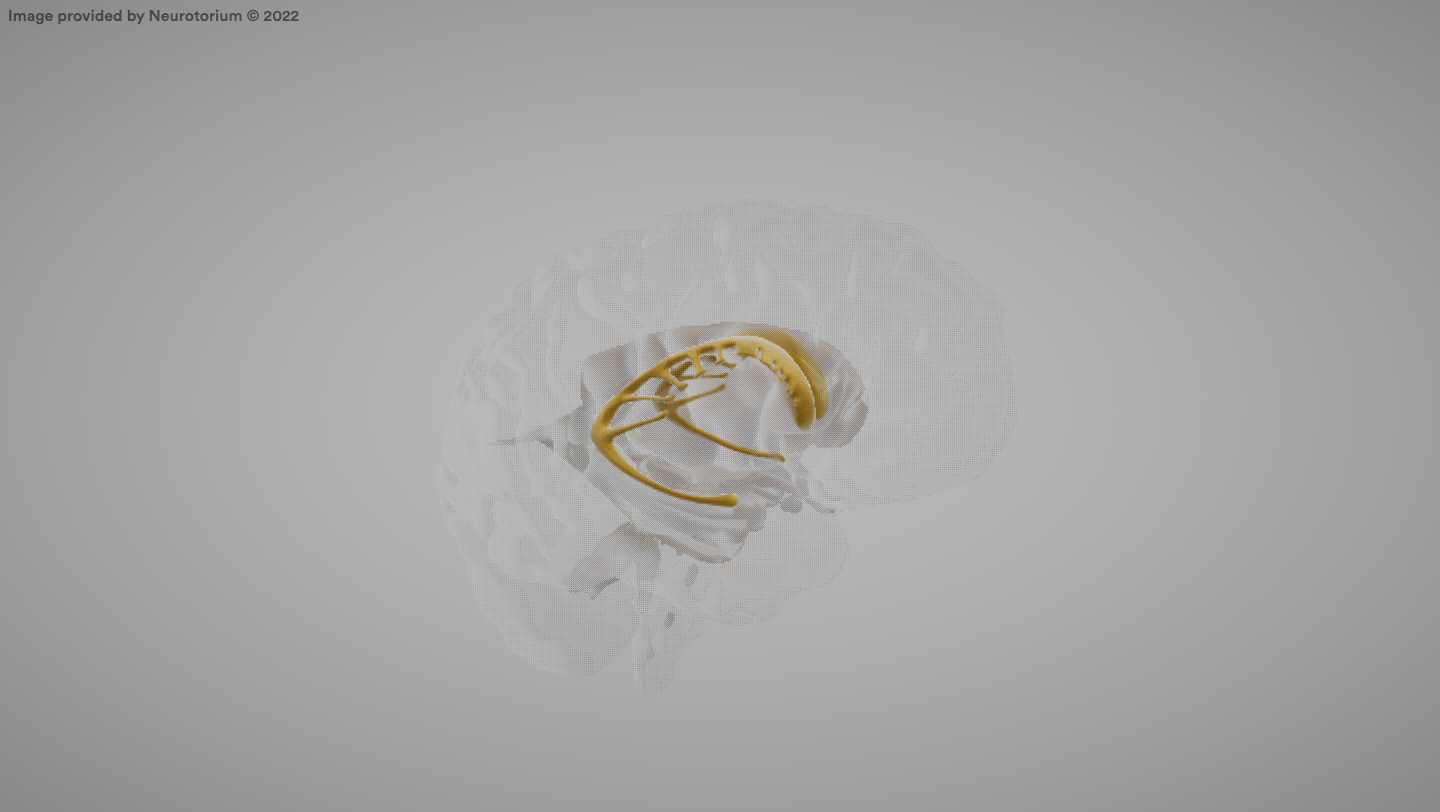

Corpus Callosum

A large bundle of nerve fibers connecting the two cerebral hemispheres.